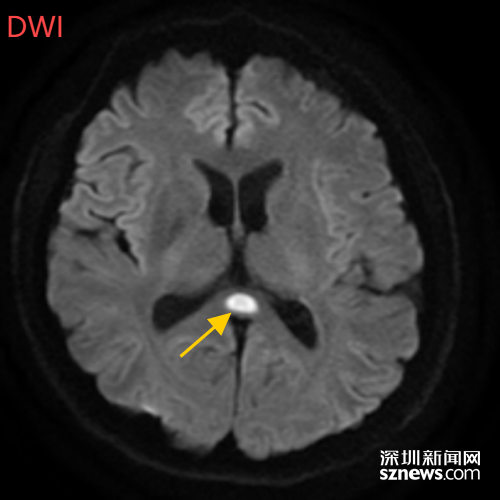

董先生再次来到南科大医院,入神经内科住院治疗。经过头部磁共振平扫、弥散、增强影像等检查,医生诊断,董先生得了比较少见的病症:可逆性胼胝体压部综合征。

(董先生的5月2日影像结果显示,胼胝体压部发生病变)

据神经内科白春艳主任医师介绍,可逆性胼胝体压部综合征以胼胝体压部短暂性病变为特征,患者可能表现为头痛、意识障碍、精神行为异常、癫痫发作等相关症状。

如果把大脑比作一座城市,胼胝体就是连接左右脑的“跨海大桥”,而胼胝体压部正是桥上的“核心枢纽”。当它因酒精、熬夜或感染“肿了”,大脑信号就会“堵车”,引发一系列“故障”。